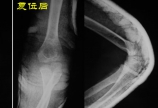

【小儿骨科】 “问倒老师系列”之八:这是儿童肘关节脱位吗?

病情概述: Childrenarenotjustsmalladults. ——Dr.MercerRang 学生:1岁4个月的男孩摔伤肘部。我考虑是“肘关节脱位”,对吗? 老师:不对,应该是transphysealfractureofthedistalhumerus/distalhumeralphysealseparat… [详情]